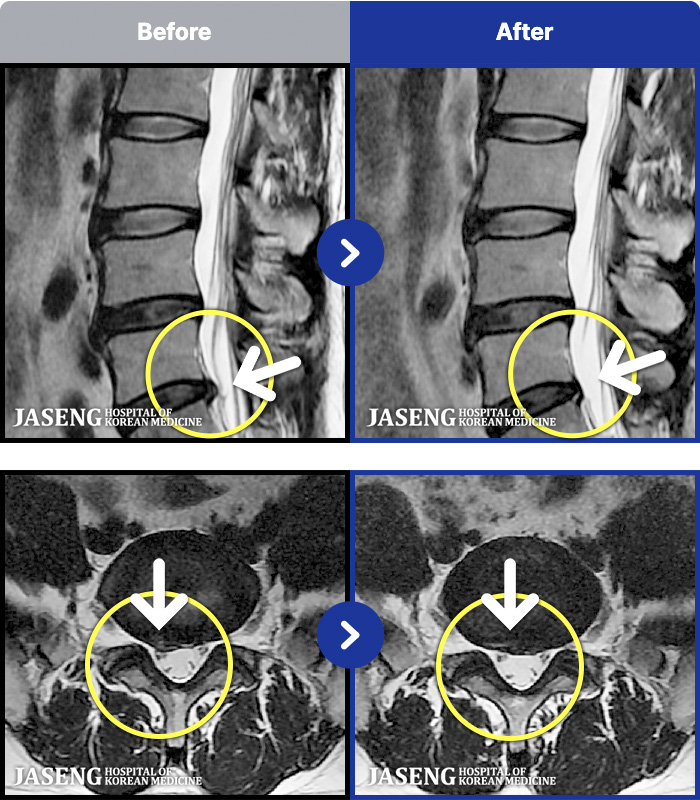

MRI ġ

1,240 MRI ũ ʸ Ȯϼ.